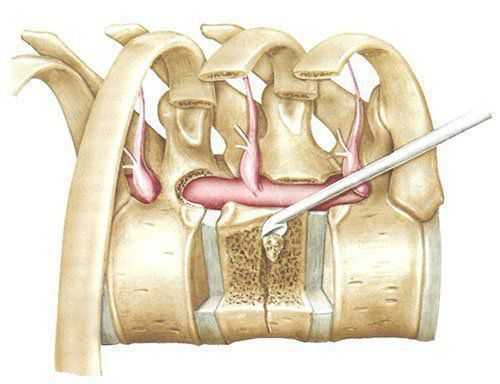

Удаление головки ребра позволяет подойти к заднебоковым отделам диска и межпозвонковым отверстиям. Оно производится кусачками и высокоскоростной дрелью после рассечения лучевых связок. Затем визуализируются ножки и межпозвонковые отверстия, ножки подтачиваются, обнажая дуральный мешок. Заднебоковые отделы тел позвонков вблизи диска скусываются или спиливаются, таким образом достигают вентрального отдела позвоночного канала (рис. 3, 4).

Рис. 3. Схема операционного поля из переднего трансторакального доступа после резекции ножек и заднебоковых отделов тела позвонка.

Рис. 4. Схема переднебокового трансторакального доступа.